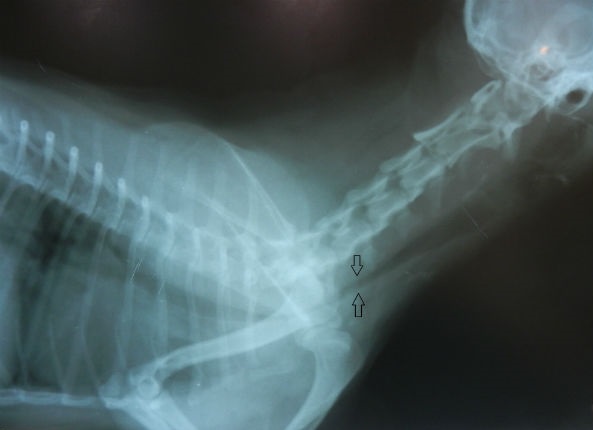

Для диагностики коллапса, ранее, стандартом считалось 2 боковых рентгеновских снимка грудной полости в разные фазы дыхания. Во время вдоха проявляется коллапс шейного отдела трахеи, во время выдоха- грудного. Из-за того, что у собак стресс при посещении ветеринара, сложно порой поймать нужную фазу дыхания и сделать снимок. Приходится делать их больше, тем самым увеличивая дозу облучения. При чрезмерном загибе вверх шеи на снимке мы увидим уплощение трахеи.

В клинике Animalia, благодаря специальному оборудованию, применяется дополнительная диагностика коллапса – эндоскопическое исследование трахеи. В этом случае можно оценить более точно степень развития коллапса. От степени будет зависеть лечение собаки.

Степеней существует 4.

1 степень- слегка провисающая верхняя мембрана(складка) трахеи (можно диагностировать только при помощи эндоскопии)

2 степень- сужение просвета трахеи на 50%

3 степень- 75%

4 степень- верхняя мембрана(складка) касается нижнего свода трахеи и выглядит как цифра 8 в горизонтальном положении.